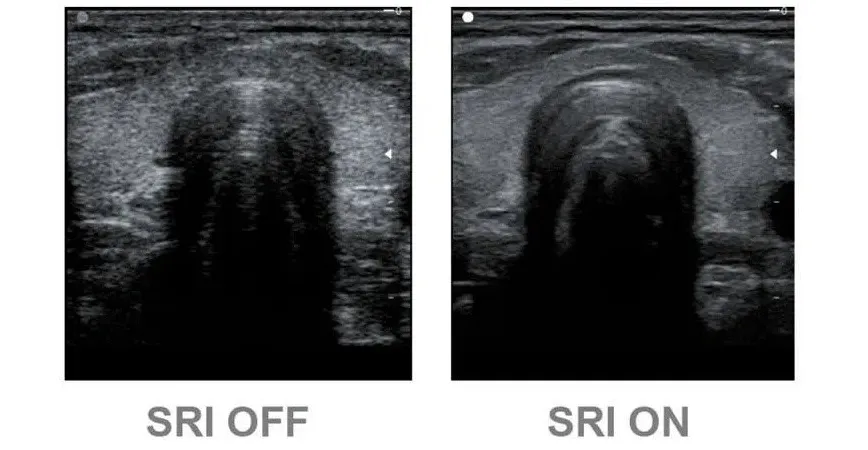

Speckle Reduction Imaging (SRI)

Технология значительно снижает количество нежелательных пятен и зернистости. В результате фильтрации улучшается связь между неоднородными участками тканей различных органов, значительно увеличивается пространственное и контрастное разрешение. Эхограмма становится более легкой для «чтения» за счет повышения качества визуализации контуров, структур тканей и мелких деталей.